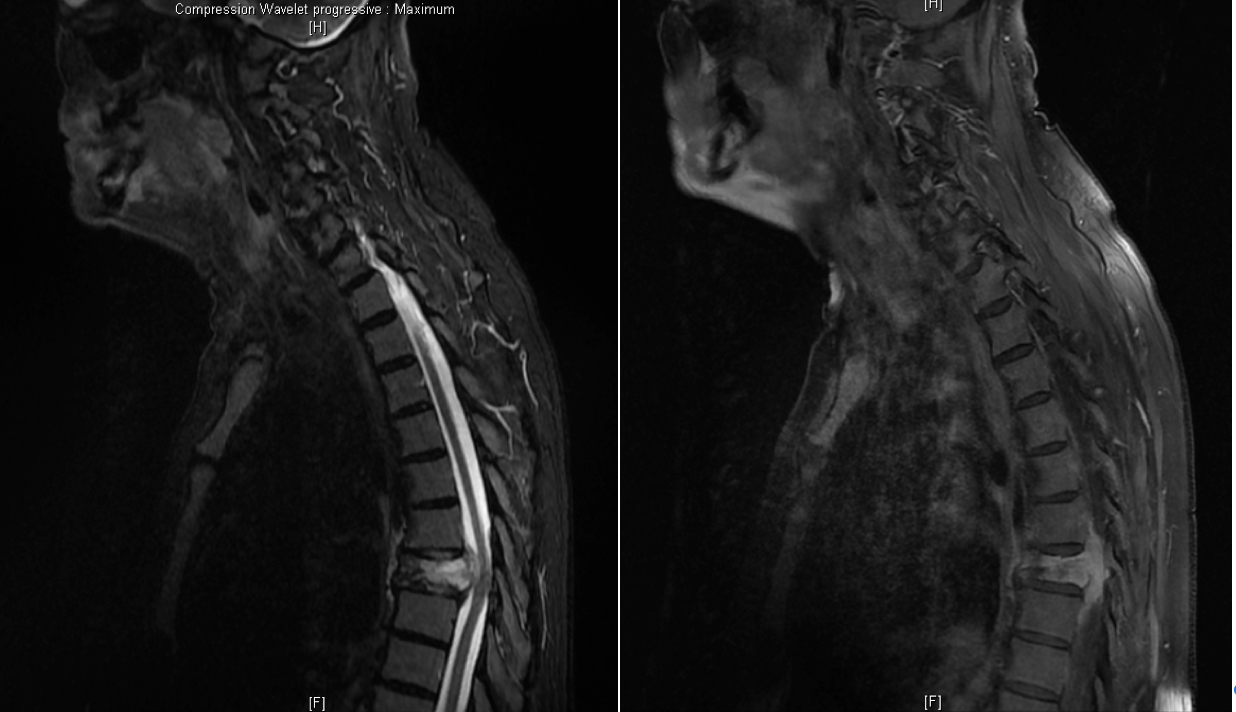

À propos de l’atteinte rachidienne vous examinez les clichés complémentaires suivants :

Question n°8 : Vous envisagez comme hypothèses diagnostiques

Même un tassement ostéoporotique peut donner un hypermétabolisme au TEP-TDM qui n’est pas spécifique

L’atteinte concerne le corps vertébral, pas le disque intervertébral

Hypothèse la plus probable dans un contexte de tumeur métastatique et devant l’unicité du tassement vertébral et l’aspect ostéolytique du les images du scanner

Le TEP-TDM n’est pas adapté à ce diagnostic, de plus l’examen neurologique est normal, ce qui exclut une compression médullaire.

Voici les résultats de l’IRM du rachis dorsal :

Question n° 11 : Vous programmez en urgence

Oui, il y a un risque majeur de compression médullaire, l’avis chirurgical doit être pris au plus vite